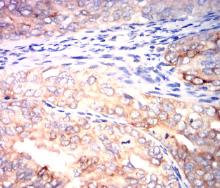

IHC    1/200-1/1000